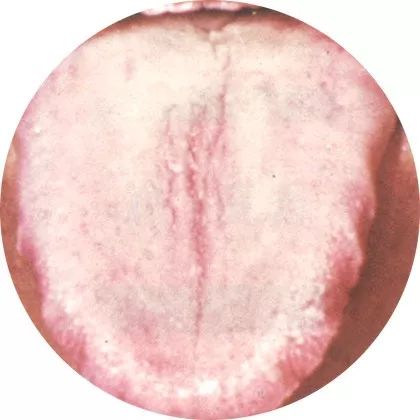

2裂纹舌:精血亏虚

裂痕中一般无舌苔覆盖,

是精血亏虚的表现。

舌苔白而又裂纹者,为精血亏虚;舌绛红而干,有裂纹者,为热盛伤津。